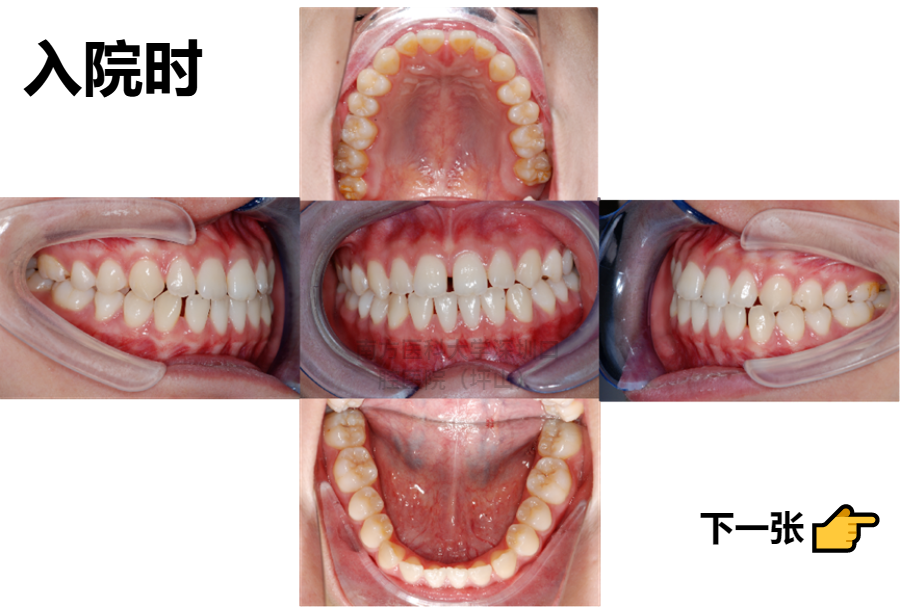

你们看,整牙前,我的牙齿中线不齐,门牙的缝隙比较大,下巴也有点歪。

以前,我每次照镜子的时候,我都觉得自己牙缝,特别是门牙牙缝太大,觉得不漂亮,没什么自信,也不敢露出牙齿笑。

你的情况是牙齿的“散在间隙”,咬合关系比较差,正常的咬合是“牙尖对牙窝”,你有点牙尖对牙尖,牙齿的中线没对齐,咬合错位造成了功能性的下颌偏斜。

经过骨性测量,医生说我本身也有一点骨性的偏斜,下颌骨的两侧长短不一样,造成了2mm左右的偏颌,也就是脸部不对称。